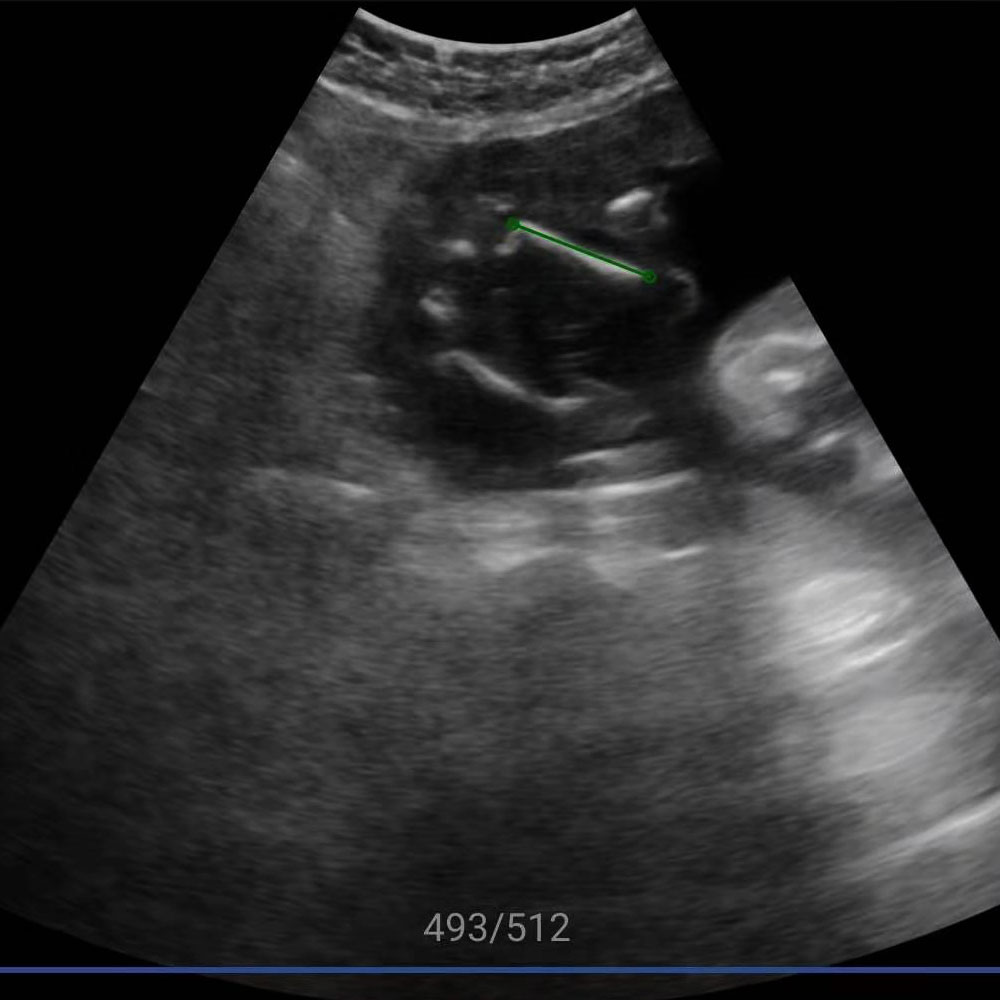

视网膜屏幕,超高分辨率。优异的图像,媲美大型超声。临床功能全面,覆盖全身

原始的超声图像像天书一样,除了专业超声医生谁都看不懂,新名医率先实现了针对超声实时动态图像的特定目标、多目标识别,准确率超过93%,超声AI数据集规模、识别准确率、移动端工程实现能力业内领先。

智能手持超声提供覆盖全身的优异图像